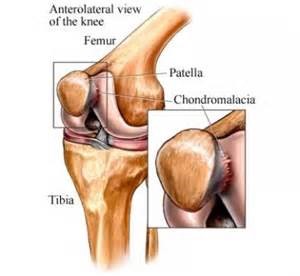

Rawatan Fisioterapi untuk Lutut Chondromalacia - PORTAL MyHEALTH

Rawatan Fisioterapi untuk Lutut Chondromalacia - PORTAL MyHEALTH

Rawatan Fisioterapi untuk Lutut Chondromalacia - PORTAL MyHEALTH

Rawatan Fisioterapi untuk Lutut Chondromalacia - PORTAL MyHEALTH